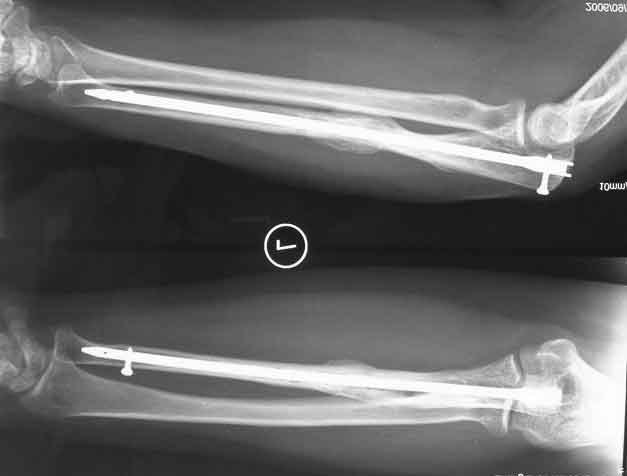

手术后的照片  尺骨带锁髓内钉治疗尺骨骨不连

病例介绍:该患者女性,27岁,经历多次钢板内固定手术失败,骨折断端有残留钉孔,骨折区骨质疏松明显,残端有吸收,为典型的萎缩型骨不连, 显然再用钉子和钢板无法固定结实,手术不断破坏血运,骨质不断减少,最后当然还是不能愈合.

我们采用带锁髓内钉治疗.打通闭塞髓腔,植入能够分散负荷的髓内针,保护了周围 骨膜血运。可以避免钢板内固定时广泛的软组织剥离,断端稳定性好,可早期功能锻炼,骨愈合率高。